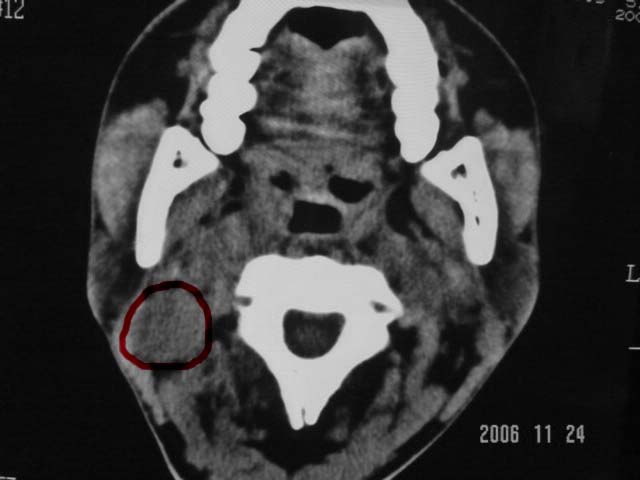

标题: CT5388:鼻塞、耳鸣3个月,涕中带血2周,颈部可触及肿大淋 [打印本页]

右侧鼻咽部软组织肿块,颅底骨质破坏,右侧颈部淋巴结肿大;诊断:鼻咽ca、右颈部淋巴结转移、颅底侵犯

右侧鼻口咽侧后壁不规则增厚,内可见密度不均匀性椭圆形软组织块影,边界欠清,咽旁间隙尚清.右颈部可见圆形软组织块影,鼻塞、耳鸣3个月,涕中带血2周,颈部可触及肿大淋巴结,考虑鼻咽癌,颈部淋巴转移.

右侧鼻咽后壁不规则增厚,内可见密度不均匀性椭圆形软组织块影,边界欠清,咽旁间隙尚清.右侧下方可见圆形软组织块影,双侧蝶窦呈均一高密度。

考虑:1、右侧鼻咽癌伴颈部淋巴结转移;

2、双侧蝶窦炎。

右侧鼻咽部软组织肿块,颅底骨质破坏,右侧颈部淋巴结肿大;诊断:右侧鼻咽ca伴右颈部淋巴结转移、颅底侵犯.

典型右侧鼻咽ca伴颈部淋巴结转移,中颅底骨侵蚀。

右侧鼻咽侧后壁不规则增厚,咽隐窝变钝,咽旁间隙变狭窄,见组织结节影[哨兵征],蝶骨似破坏,蝶窦内充塞软组织影,翼内外肌上分间隙模糊,右颈后三角区淋巴结肿大,右侧乳突增高气房消失。考虑鼻咽癌伴蝶窦侵犯及淋巴结转移,右侧浆液性中耳炎。其他恶性病变待排。

右侧鼻咽癌伴同侧颈部淋巴结转移可能性大.要是有骨窗,能看到更多征象,有助于诊断